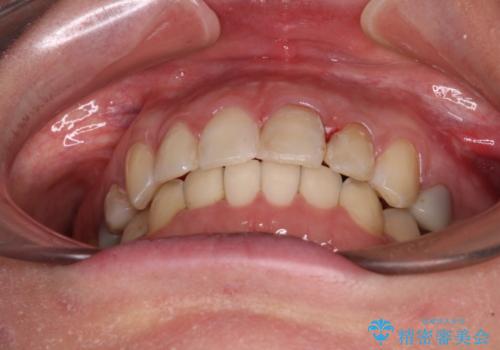

【モニター】前歯のデコボコと奥歯の虫歯 インビザライン治療と奥歯のセラミック治療

- 前歯のデコボコと奥歯の虫歯を気にして来院された患者様です。

主に下顎歯列全体の後方移動とIPR(歯と歯の間を削る)によってデコボコが解消するように設計し、インビザラインにより治療を行うこととしました。

下顎前歯の叢生が速やかに改善されたため、1年3か月で治療を終えることができました。

下顎前歯は後戻りを起こしやすいため、舌側を細いワイヤーで固定することで後戻り対策を行っています。